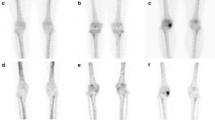

The objective was to compare the sensitivities for diagnosis of avascular necrosis of the femoral head of bone scintigraphy equipped with a pinhole collimator and with an high resolution parallel collimator. Bone scintigraphy equipped with a pinhole collimator and with an high resolution parallel collimator were performed in 16 patients with bilateral (n=7) or unilateral (n=9) avascular necrosis of the femoral head. Bone scintigraphy equipped with a pinhole collimator documented a photopenic defect in 78.3% of the necrotic hips, while bone scintigraphy equipped with an high resolution parallel collimator documented a defect in 47.8%. There was no false-positive diagnosis of avascular necrosis of the femoral head on either bone scintigraphy equipped with a pinhole or with an high resolution parallel collimator. In conclusion, bone scintigraphy equipped with a pinhole collimator has a greater sensitivity for diagnosis of avascular necrosis of the femoral head than bone scintigraphy equipped with an high resolution parallel collimator.